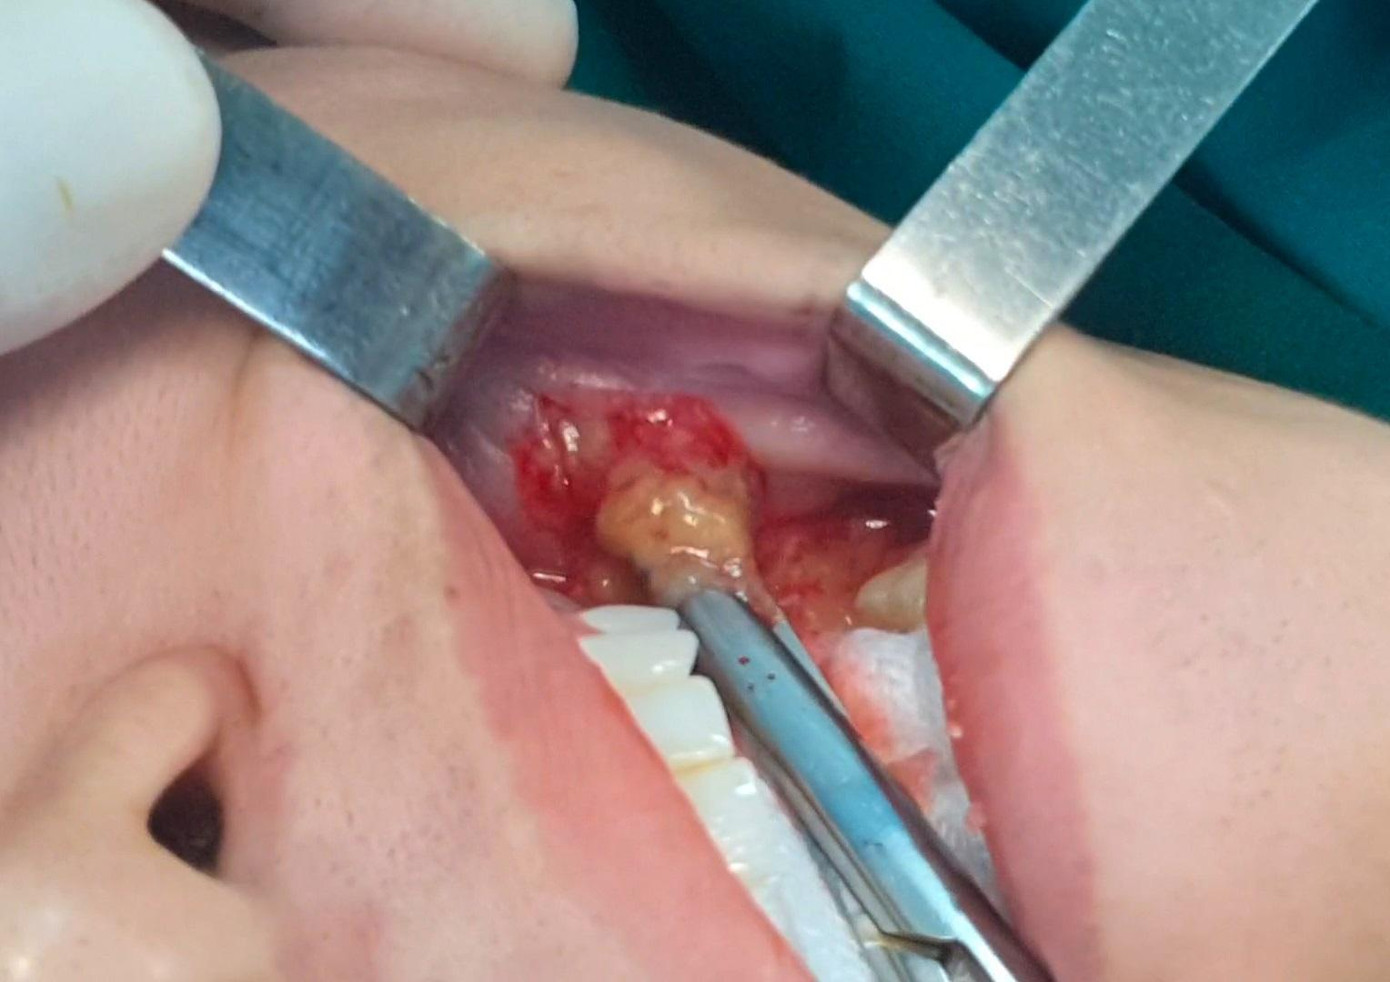

| Các bác sĩ đã phải thực hiện cuộc phẫu thuật khẩn để ngăn chặn nhiễm trùng, hoại tử lan rộng |

Qua thăm khám, bác sĩ ghi nhận hai bên má bệnh nhân bị nhiễm trùng, tụ dịch thành khối áp xe. Ổ mủ đã ăn sâu vào các mô cơ trên mặt, filler len lỏi khắp mô cơ, ổ áp xe má bên phải hoại tử nghiêm trọng. Để tránh nguy cơ hoại tử lan rộng gây nhiễm trùng huyết đe dọa tính mạng người bệnh, các bác sĩ đã quyết định phẫu thuật khẩn.

Suốt 3 giờ trong phòng mổ, BS Tú Dung cùng ê kíp đã nạo hút toàn bộ ổ áp xe, dịch mủ trên hai bên má của bệnh nhân, lấy ra rất nhiều dịch mủ lẫn máu và các khối vón cục dưới da. Dù đã cố gắng để hạn chế tối đa tác động của phẫu thuật đến tính thẩm mỹ của gương mặt người bệnh, tuy nhiên sau phẫu thuật các bác sĩ tiên lượng gương mặt của bệnh nhân sẽ xuất hiện nhiều vị trí lồi lõm bất thường cần phải tái tạo sau khi bình phục vết thương.